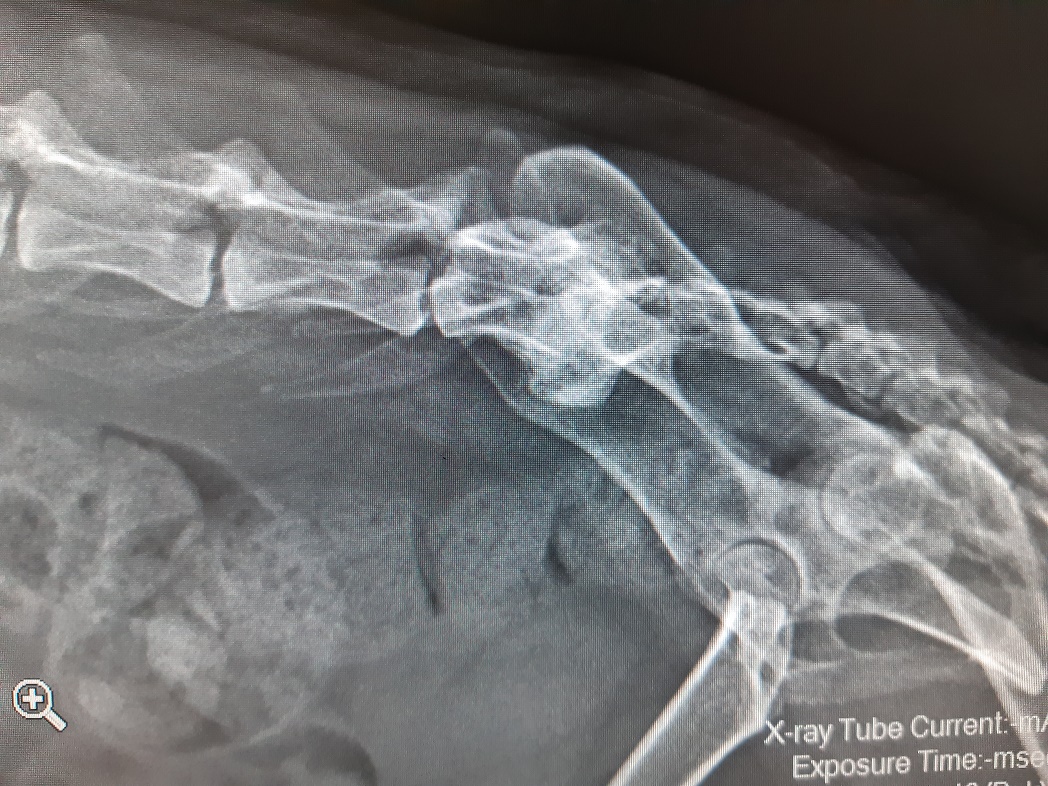

Ein kleiner Rückblick noch auf den Dezember, der uns viele interessante Patienten gebracht hat!